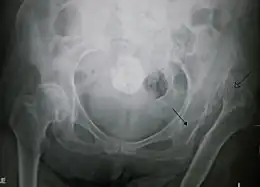

Radiographie montrant une luxation complète de la hanche gauche chez une personne âgée.